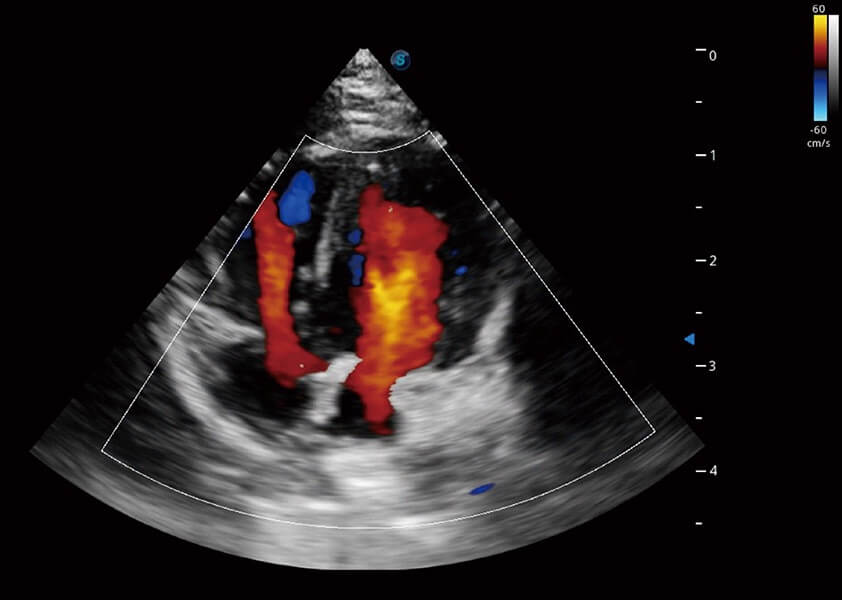

ProPet 60 作為一款高端臺(tái)式動(dòng)物超聲設(shè)備,為動(dòng)物醫(yī)生的日常診斷提供了一系列貼合動(dòng)物臨床需求、解決臨床實(shí)際問題的高級成像功能。憑借全系列高清探頭,滿足醫(yī)生對腹部、心臟、生殖、淺表、肌骨等成像的所有需求,切實(shí)幫助您提升檢查效率,提高診斷信心。